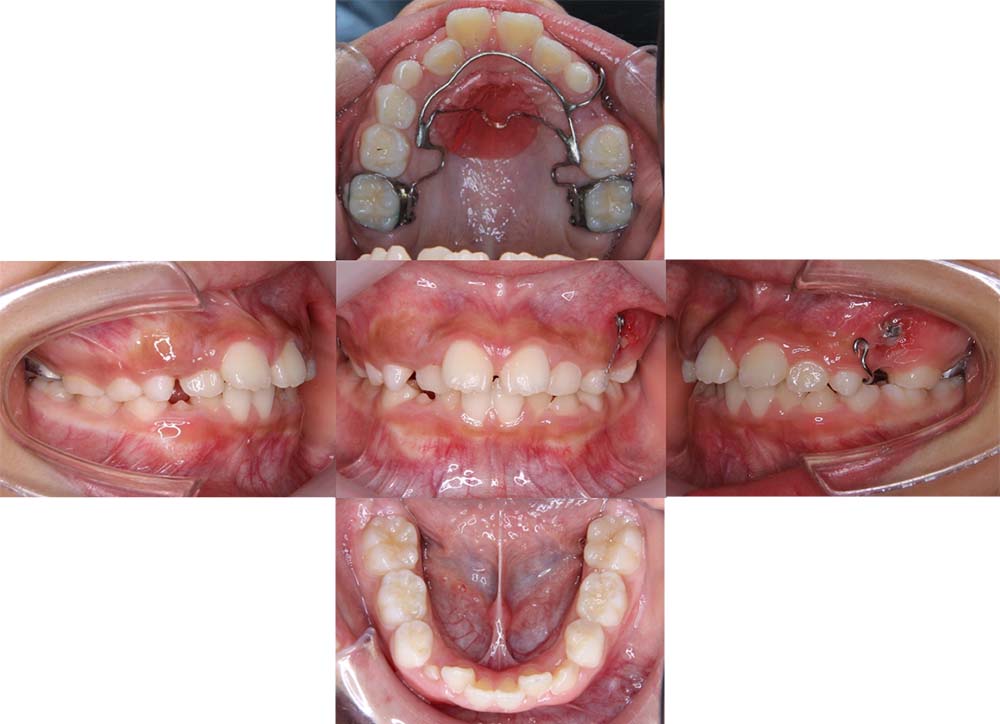

症例10

| 主訴 | 前歯が反対に噛んでいる |

| 診断名あるいは主な症状 | 反対咬合 |

| 年齢/性別 | 9歳・男児 |

| 矯正ステージ | 子どもの矯正治療 |

| 治療方法 | リンガルアーチ |

| 抜歯部位/抜歯有無 | – |

|---|---|

| 治療内容 | リンガルアーチにて反対咬合を改善。その後は成長と生え変わりの定期的なチェックを行った。 |

| 費用 | 30万円程度(2025.5での料金となります。) |

| 治療期間 | 1年0ヶ月程度 |

| 主なリスク・副作用 | 痛み、歯根吸収、歯肉退縮、虫歯、後戻り |